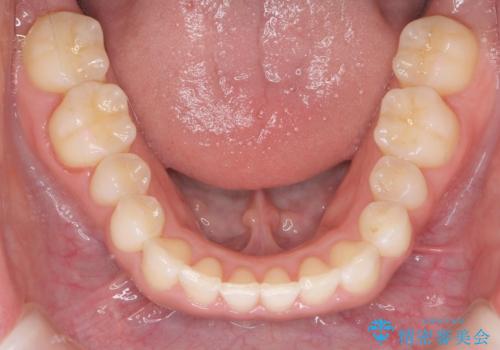

八重歯を非抜歯で マウスピースで治療 奥歯を後ろに下げてすき間を確保

奥歯を後ろに下げてすき間を確保し、八重歯を引っ込めて並べる治療を行いました。

かなり真面目に使っていただいた印象で、綺麗に動きました。